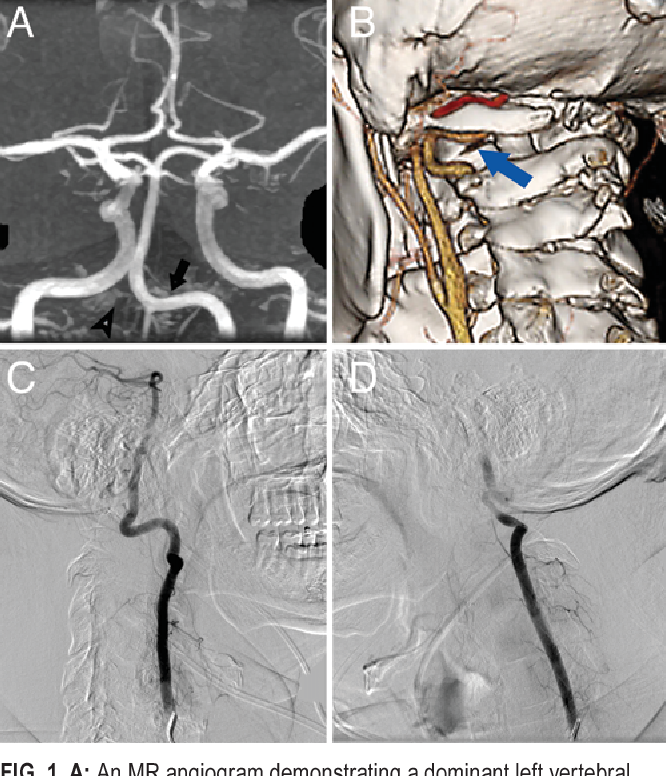

1/ هناك سبب نادر من أسباب الدوار يسمى متلازمة الشريان الفقري الدوراني Rotational vertebral artery syndrome سأتحدث عنها في هذا الثريد

الصورة المرفقة توضح مظهر هذه المشكلة في الأشعة المختلفة